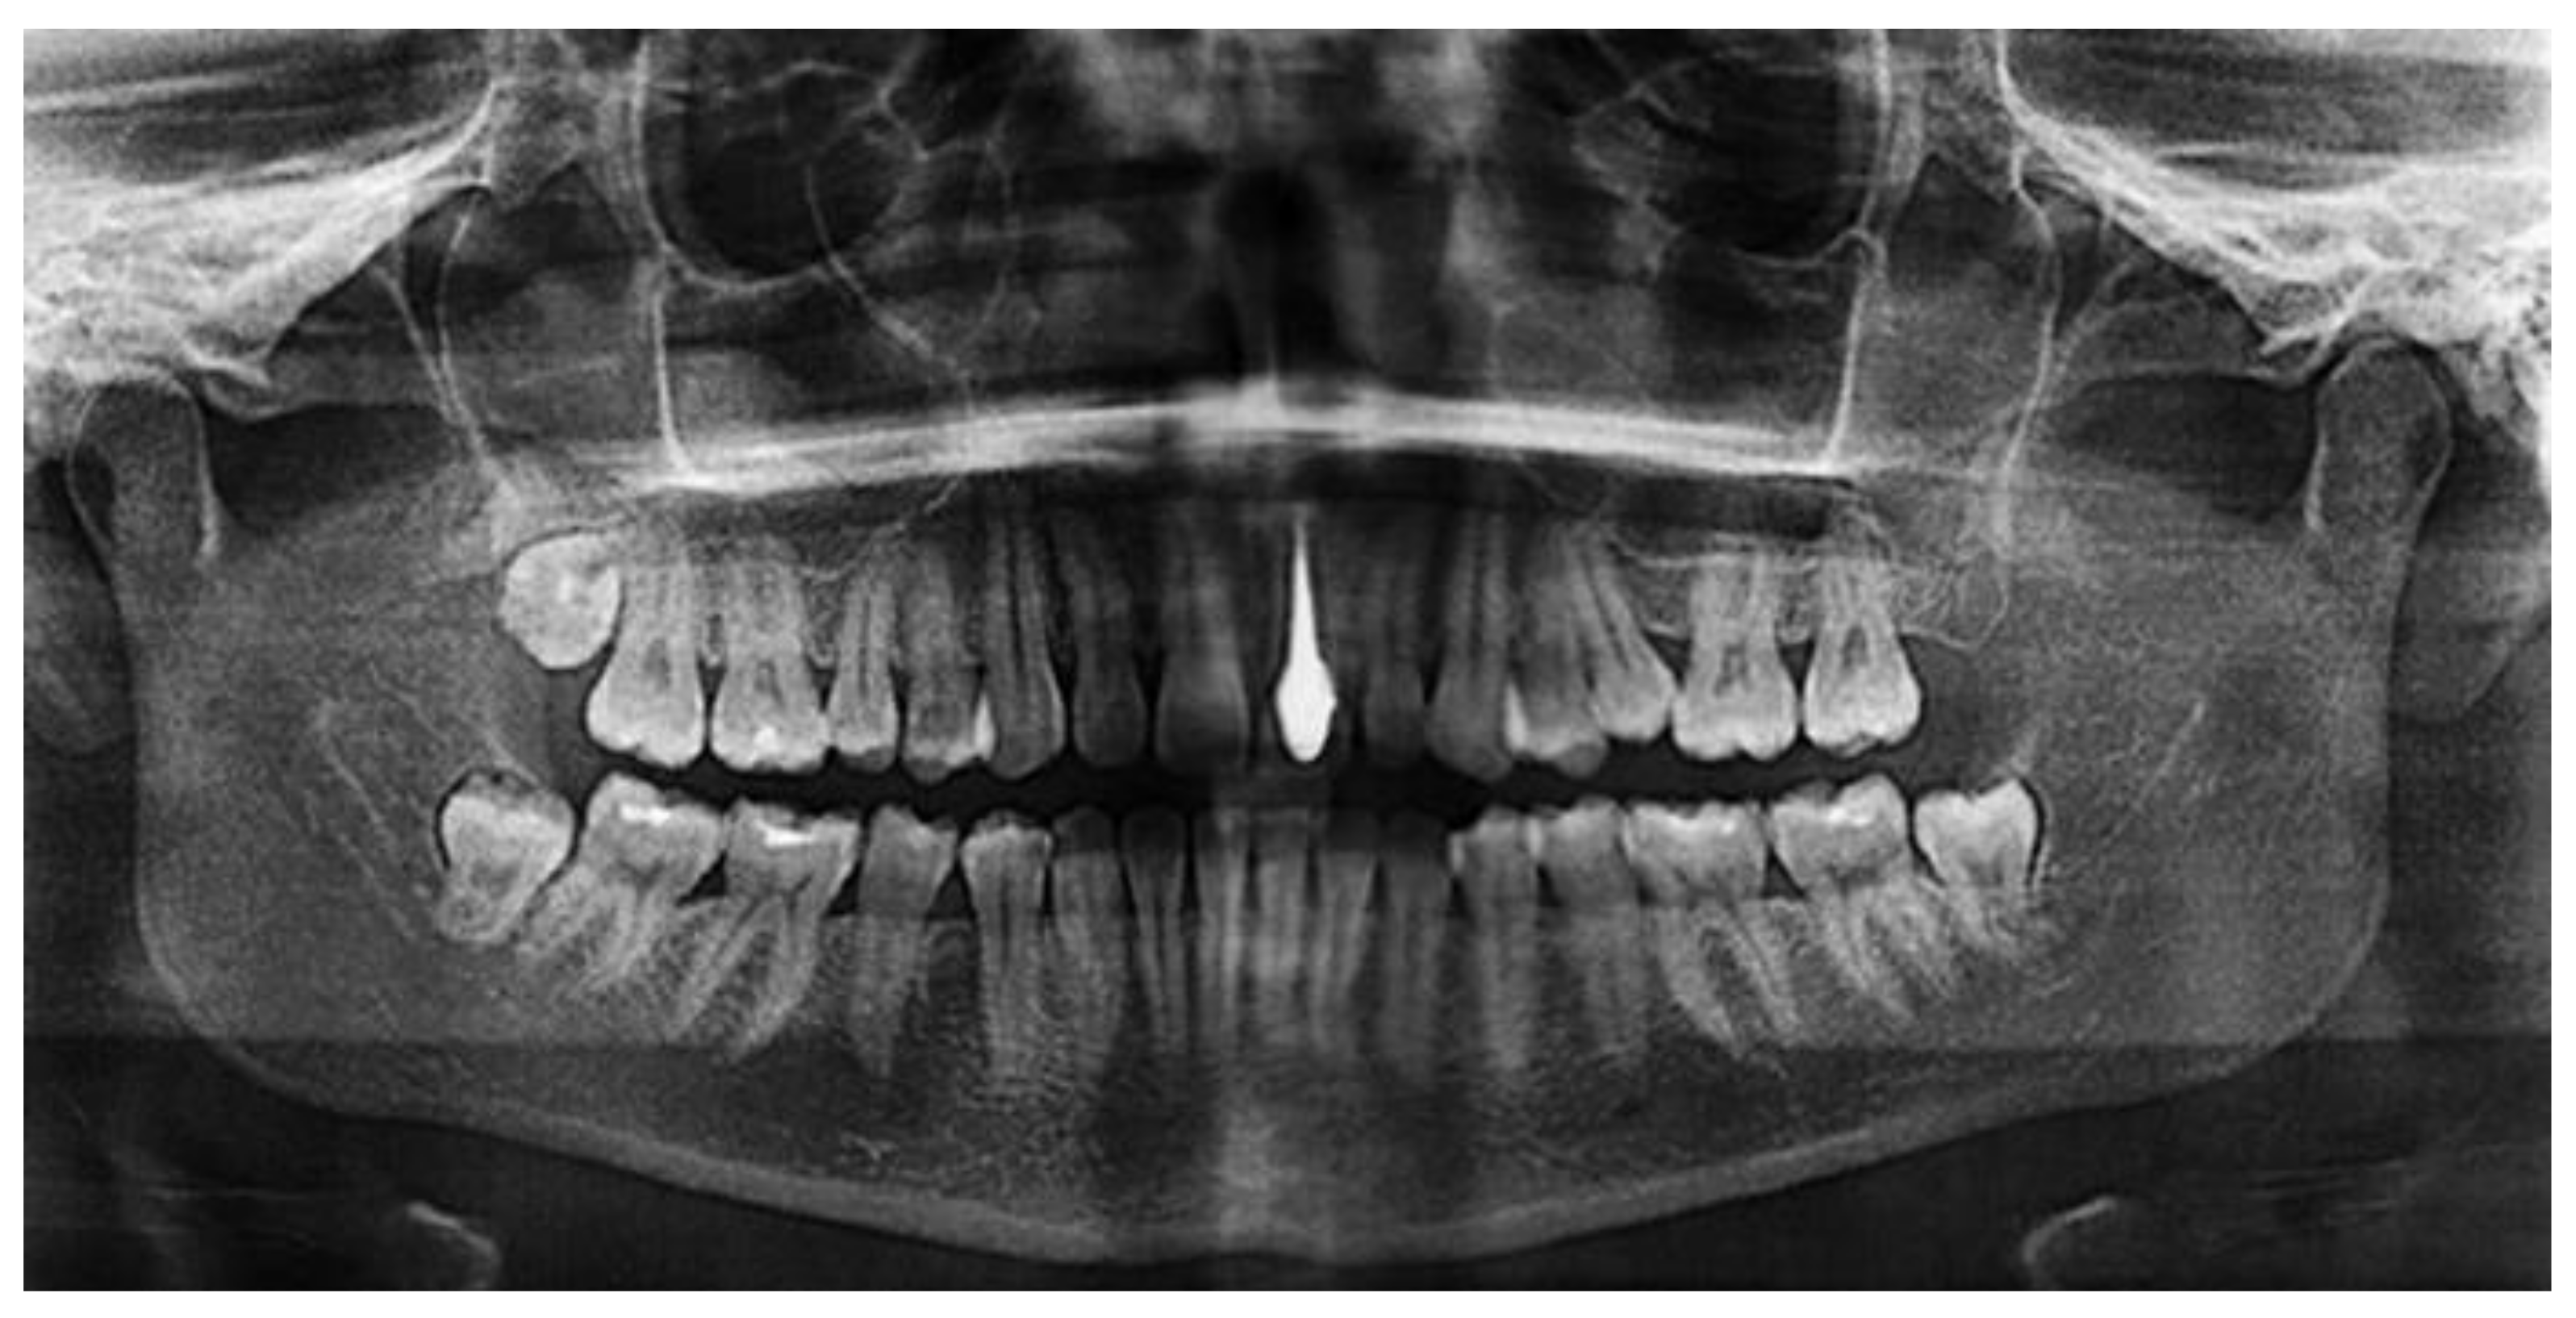

An earlier study [62] investigated the potential use of porous silicon nitride for all-ceramic dental restorations as a core material and results were compared with those of a commercial ZrO2 ceramic. The color of silicon nitride could be tailored by the porosity introduced and a color shade suitable for restorative applications was obtained. The flexural strength of Si3N4 was found to be 418 MPa despite an open porosity of nearly 10.5% (cp. Table 1). This rather high strength may be related to the strong neck formation between β-Si3N4 grains, the intertwined distribution of these grains, and the crack deflection potential of rod-like β-Si3N4. The Vickers hardness of Si3N4 was found to be 10.9 MPa whereas ZrO2 had 13.7 MPa, which reduces the risk of the wear of opposing natural teeth. Shear bond strength to dentin was tested and indicated low values for silicon nitride without a coupling agent (2.24 ± 1.15 MPa), which strongly increased by adding a silane coupling agent to 8.44 ± 2.98 MPa, suggesting that the usage of coupling agents for Si3N4 is essential. The radiolucent behavior of Si3N4 will enable for both the restorations and the surrounding tissues to be imaged using plain radiography (Figure 6). Hence, this study shows that with the tailored manufacturing methods including additive manufacturing, silicon nitride can be considered an effective dental restorative material.

Figure 6.

Silicon nitride as a material for dental core restoration, revealing radiolucency [63]. © Creative Commons Attribution 4.0 International License.